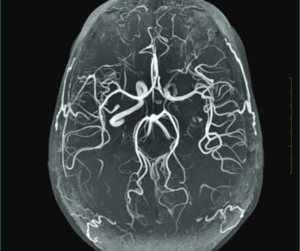

Magnetic resonance angiography of the brain is a non-invasive, painless diagnostic imaging procedure using radio waves and a strong magnetic field to create detailed images of the blood vessels in your brain.

An MR Angio (MRA) of the brain is a non-invasive imaging scan that primarily diagnoses issues related to the brain’s blood vessels and circulation.